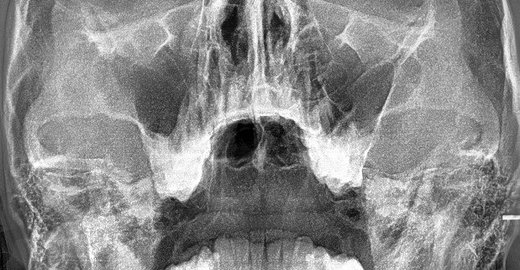

Рентгенография небного шва: Медицинские исследования и диагностика

Раздел: Фотопутеводитель